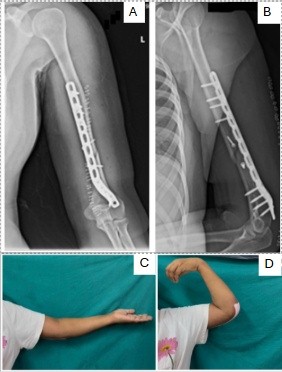

Following American College of Obstetricians and Gynecologists (ACOG) recommendations for fetal monitoring in viable pregnancies requiring surgery, continuous CTG surveillance was carried out. As fetal distress was evident on Doppler and non-stress tests, definitive orthopedic intervention was deferred. Conservative immobilization was maintained with analgesia using paracetamol. However, humeral fractures do not interfere with the mechanics of vaginal delivery, as is often the case with unstable pelvic fractures [5]. The presence of fetal distress in this patient necessitated an emergency cesarean section. At 38 + 4 weeks of gestation, an emergency LSCS was performed under spinal anesthesia. Intraoperatively, the lower uterine segment was well-formed. Amniotic fluid was blood-stained but adequate. The placenta was removed completely with intact membranes. Bilateral fallopian tubes and ovaries appeared normal. The uterus was closed in two layers with hemostasis achieved. Estimated blood loss was 500 mL. A healthy neonate weighing 3005 g was delivered without complications. A neonatal team was on standby, in accordance with standard care for non-obstetric surgery during viable pregnancies [6]. CTG monitoring during and after the procedure remained reassuring. A Kleihauer–Betke test was performed to assess the risk of fetomaternal hemorrhage as per trauma protocol [7]. On post-operative day 4, the patient underwent open reduction and internal fixation (ORIF) of the right humerus using an 8-hole extra-articular distal humerus locking plate with two lag screws. A standard anterolateral approach was used. The fracture site was visualized, and anatomical reduction was achieved without neurovascular compromise. General anesthesia was induced with propofol and fentanyl. In addition, an ultrasound-guided right supraclavicular brachial plexus block with ropivacaine was administered to optimize post-operative pain relief [8]. This combined anesthetic strategy was chosen to minimize intraoperative and post-operative opioid use, particularly to reduce neonatal drug exposure during lactation [9].

The patient had an uneventful post-operative recovery. Early mobilization of the shoulder and elbow was initiated within 36 h (Figure 2).

Figure 2: Post-operative radiographs of the left humerus following open reduction and internal fixation, anteroposterior (a) and lateral views (b) showing fracture fixation with distal humerus extra-articular plate and two lag screw, and clinical images showing post-operative range of motion of left elbow extension (c) and flexion (d).